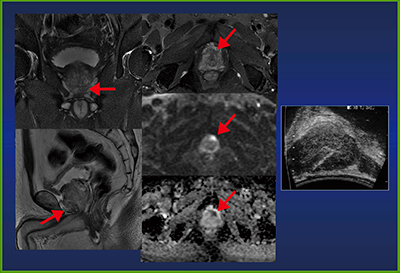

従前の前立腺癌の生検は,TRUS下に数か所〜十数か所の組織をランダムに採取していたが,最近ではMRIで事前に病変を検出し,TRUSとMRIのフュージョン画像やMR画像ガイド下にターゲットバイオプシーを実施することで,診断能の向上を図ることが可能になっている(図6)。

図6 生検前MRIで腫瘍の位置情報などを提供することで

前立腺癌の検出率が向上